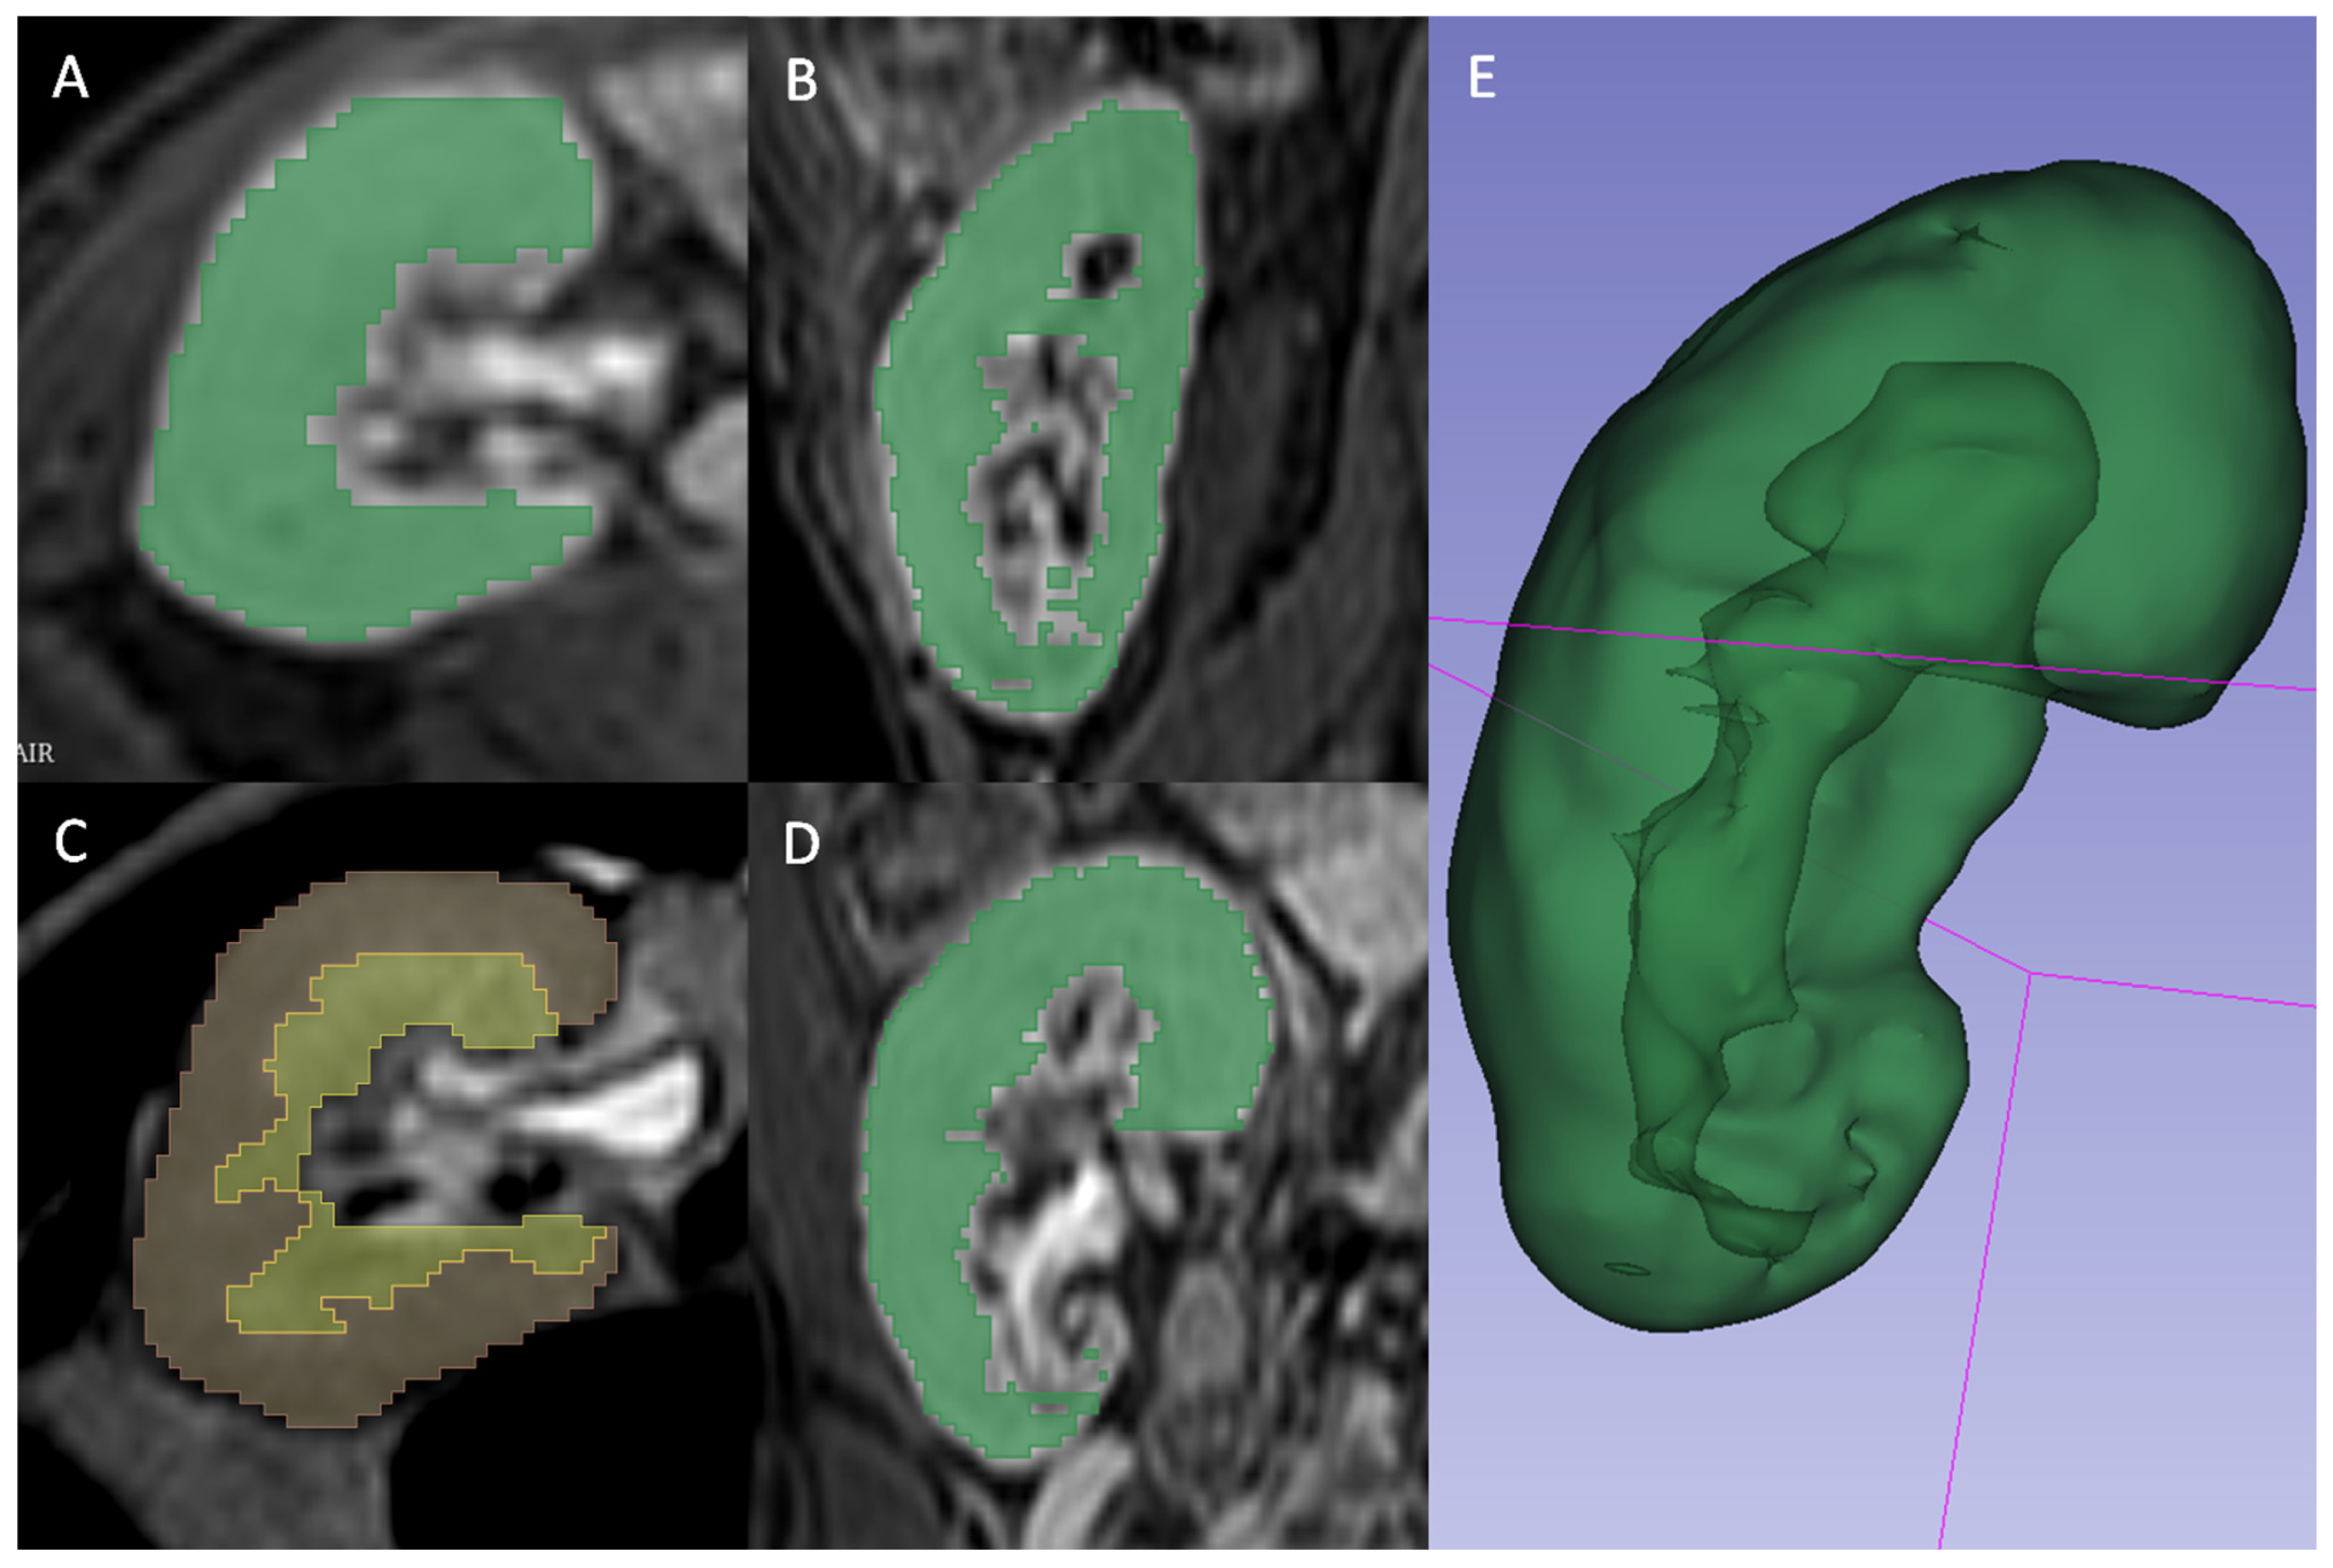

3.4. Machine Learning Model Performances

Model performances are reported in Table 3, providing AUCs with respective 95% CI for IFTA ≥ 50% and ≥25% both in training and in test sets. The models showed a better performance for IFTA ≥ 50%. Radiomics performed slightly better than clinical-only models, and models using both radiomic and clinical variables showed a marked increase in AUC. Models showed higher AUCs, especially for IFTA ≥ 50%, in the training set than in the test set. The decrease in AUC from training to test set was particularly significant for the model, including both radiomic and clinic characteristics (for IFTA ≥ 50%, AUC 0.96, 95%CI 0.84–0.98, and 0.86, 95% CI 0.41–0.99, for the training and test set, respectively) (Figure 3).

Figure 3. AUC of the two models based on clinical, radiomic and mixed model. (A,C) AUC obtained using an internal 10-fold cross validation method on the training cohort ((A) IFTA ≥ 25%, (C) IFTA ≥ 50%). (B,D) AUC obtained applying models deployed on training cohort to a validation cohort composed by new tests ((B) IFTA ≥ 25%, (D) IFTA ≥ 50%).